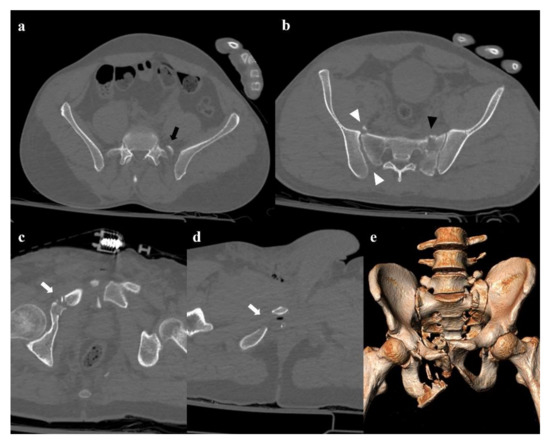

17 pages, 55736 KB

Imaging Review of Pelvic Ring Fractures and Its Complications in High-Energy Trauma

by Edoardo Leone, Andrea Garipoli, Umberto Ripani, Riccardo Maria Lanzetti, Marco Spoliti, Domenico Creta, Carolina Giannace, Antonio Galluzzo, Margherita Trinci and Michele Galluzzo

Pelvic ring fractures are common in high-energy blunt trauma, especially in traffic accidents. These types of injuries have a high rate of morbidity and mortality, due to the common instability of the fractures, and the associated intrapelvic vascular and visceral complications. Computed tomography [...] Read more.

Pelvic ring fractures are common in high-energy blunt trauma, especially in traffic accidents. These types of injuries have a high rate of morbidity and mortality, due to the common instability of the fractures, and the associated intrapelvic vascular and visceral complications. Computed tomography (CT) is the gold standard technique in the evaluation of pelvic trauma because it can quickly and accurately identify pelvic ring fractures, intrapelvic active bleeding, and lesions of other body systems. To properly guide the multidisciplinary management of the polytrauma patient, a classification criterion is mandatory. In this review, we decided to focus on the Young and Burgess classification, because it combines the mechanism and the stability of the fractures, helping to accurately identify injuries and related complications. Full article